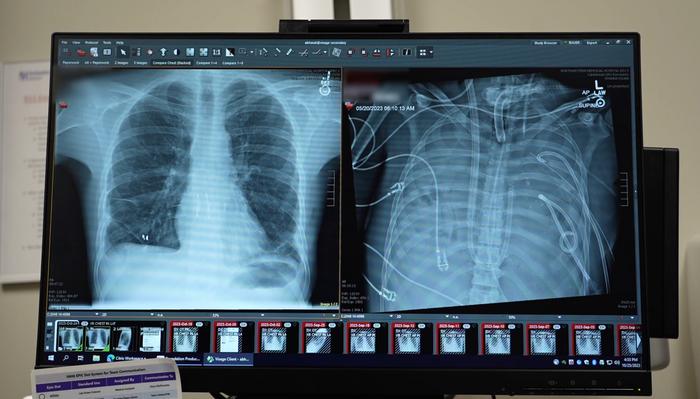

The patients’ new lungs (left) and old lungs (right).

view moreCredit: Northwestern Medicine